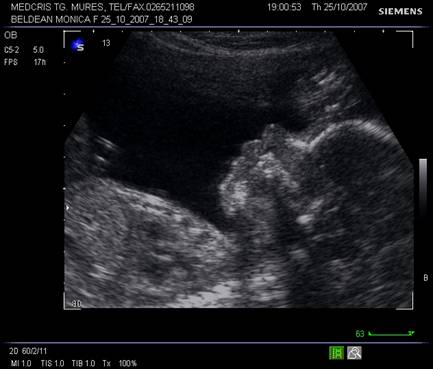

Planul VIII defineste profilul fetal in pozitie occipitoposterioara. Profilul de-vine vizibil de la sfarsitul trim I. In aceasta sectiune se pot oserva miscarile fiziologice fetale de deschidere a gurii, miscarea limbii, inghitirea, aspiratia de lichid amniotic.

Pozitia favorabila fetala poate pune in evidenta cavum septum pellucidi, corpus calosum (dupa 20 de sapt), lamina tecti, pons sau cerebellum.

Fig. nr.158 Profil fetal in pozitie occipitoposterioara, corespunzator planului VIII